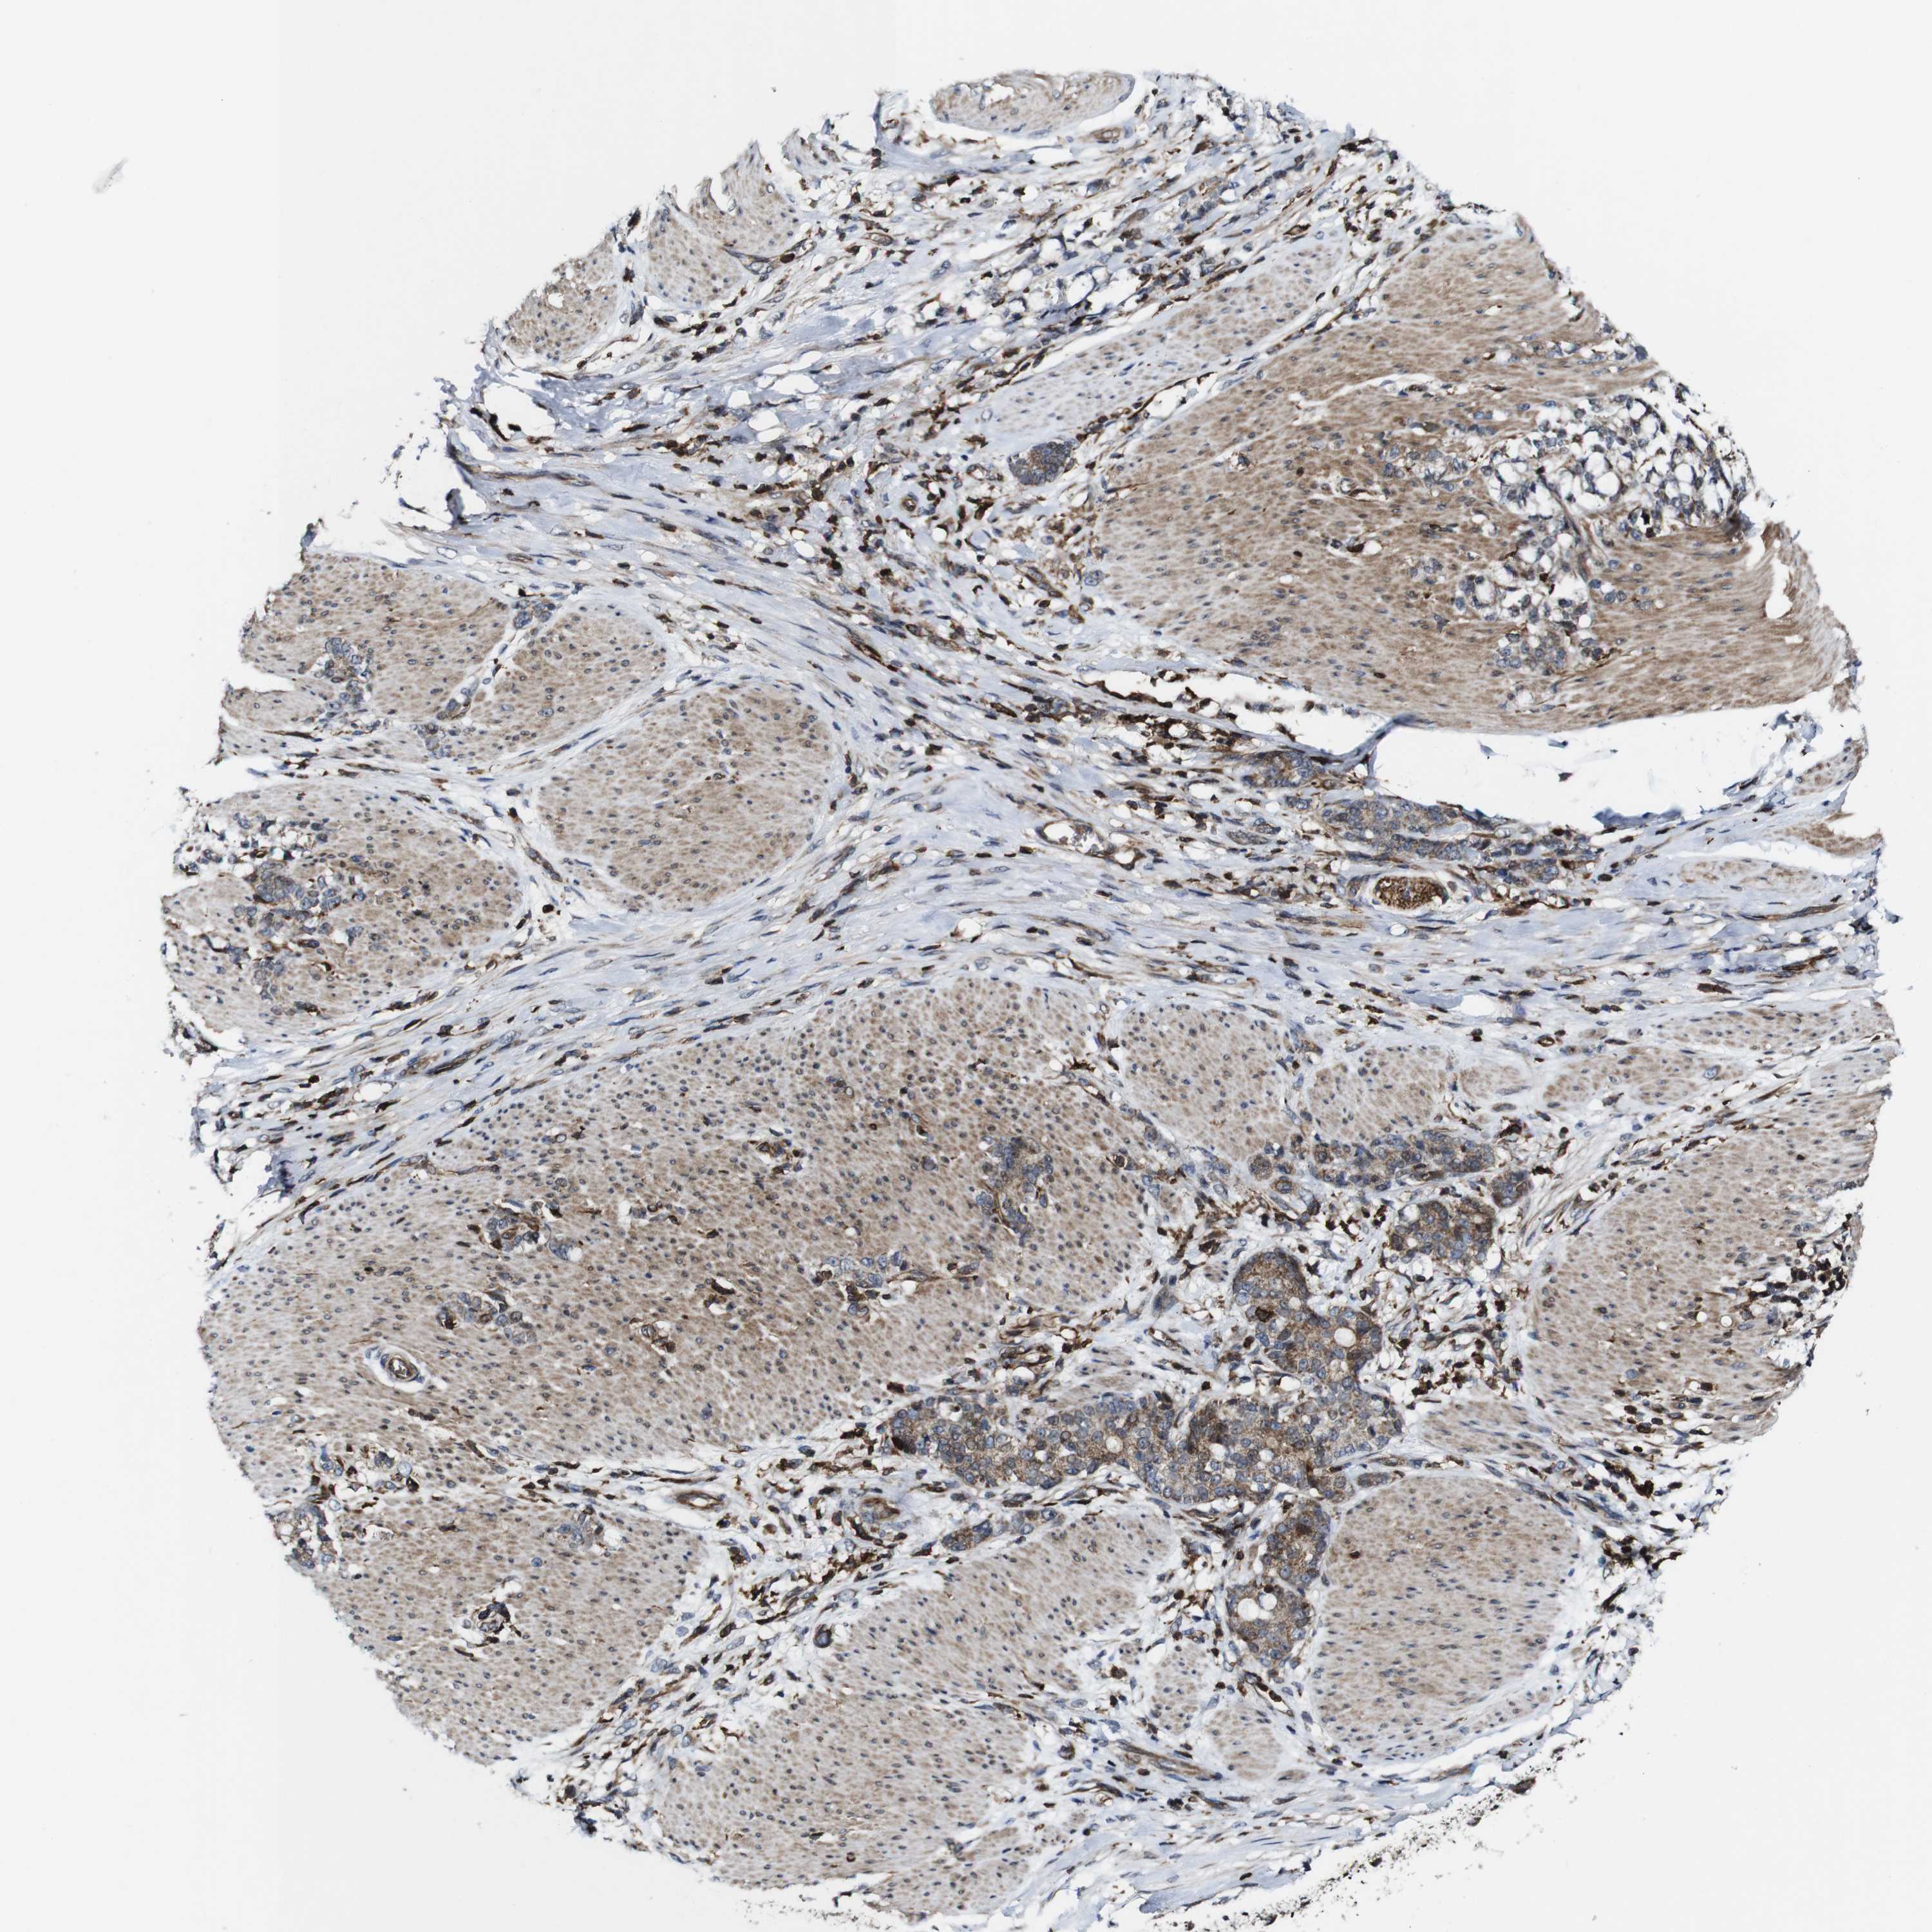

STOMACH CANCER - Protein expressioni

A mouse-over function shows sample information and annotation data. Click on an image to view it in a full screen mode. Samples can be filtered based on level of antibody staining by selecting one or several of the following categories: high, medium, low and not detected. The assay and annotation is described here.

Note that samples used for immunohistochemistry by the Human Protein Atlas do not correspond to samples in the TCGA dataset.

Antibody stainingi

Antibody staining in the annotated cell types in the current human tissue is reported as not detected, low, medium, or high, based on conventional immunohistochemistry profiling in selected tissues. This score is based on the combination of the staining intensity and fraction of stained cells.

Each image is clickable and will lead to virtual microscopy that enables deeper exploration of all samples and also displays staining intensity scores, fraction scores and subcellular localization as well as patient and tissue information for each sample.

Antibody HPA040820

Antibody CAB013089

Staining

High

Medium

Low

Not detected

Intensity

Strong

Moderate

Weak

Negative

Quantity

>75%

75%-25%

<25%

None

Location

Nuclear

Cytoplasmic/membranous

Cytoplasmic/membranous,nuclear

Adenocarcinoma, NOS